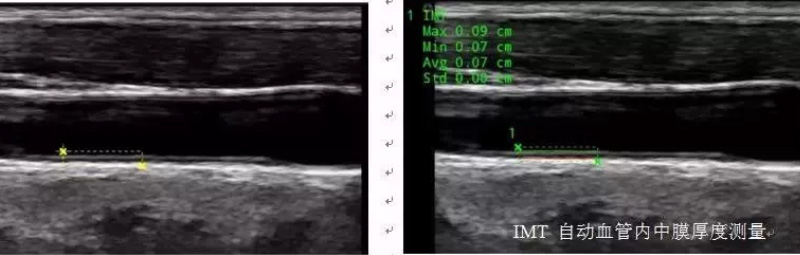

血管應用方面,自動IMT與手動測量相比提高了準確性,更快速更方便。系統(tǒng)可以自動描記并顯示結果。